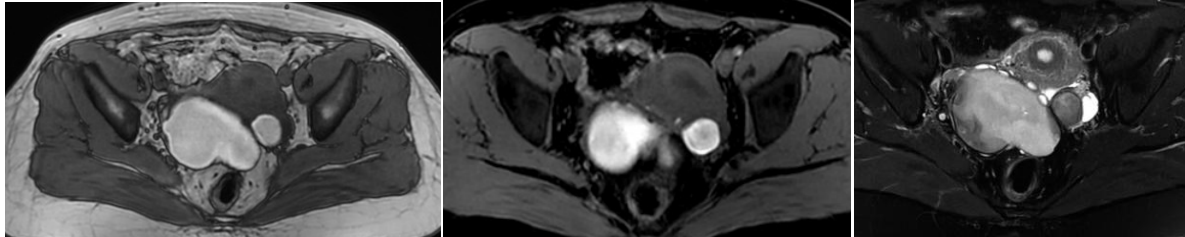

颗粒细胞瘤一般伴有雌激素水平增高症状,如月经紊乱、量多,绝经后阴道出血等,常合并子宫内膜增厚,影像表现为多房囊性占位,典型者呈海绵状、蜂窝状,囊较小,出血常见,常伴液平,实性成分及囊壁中等强化。

45岁,颗粒细胞瘤